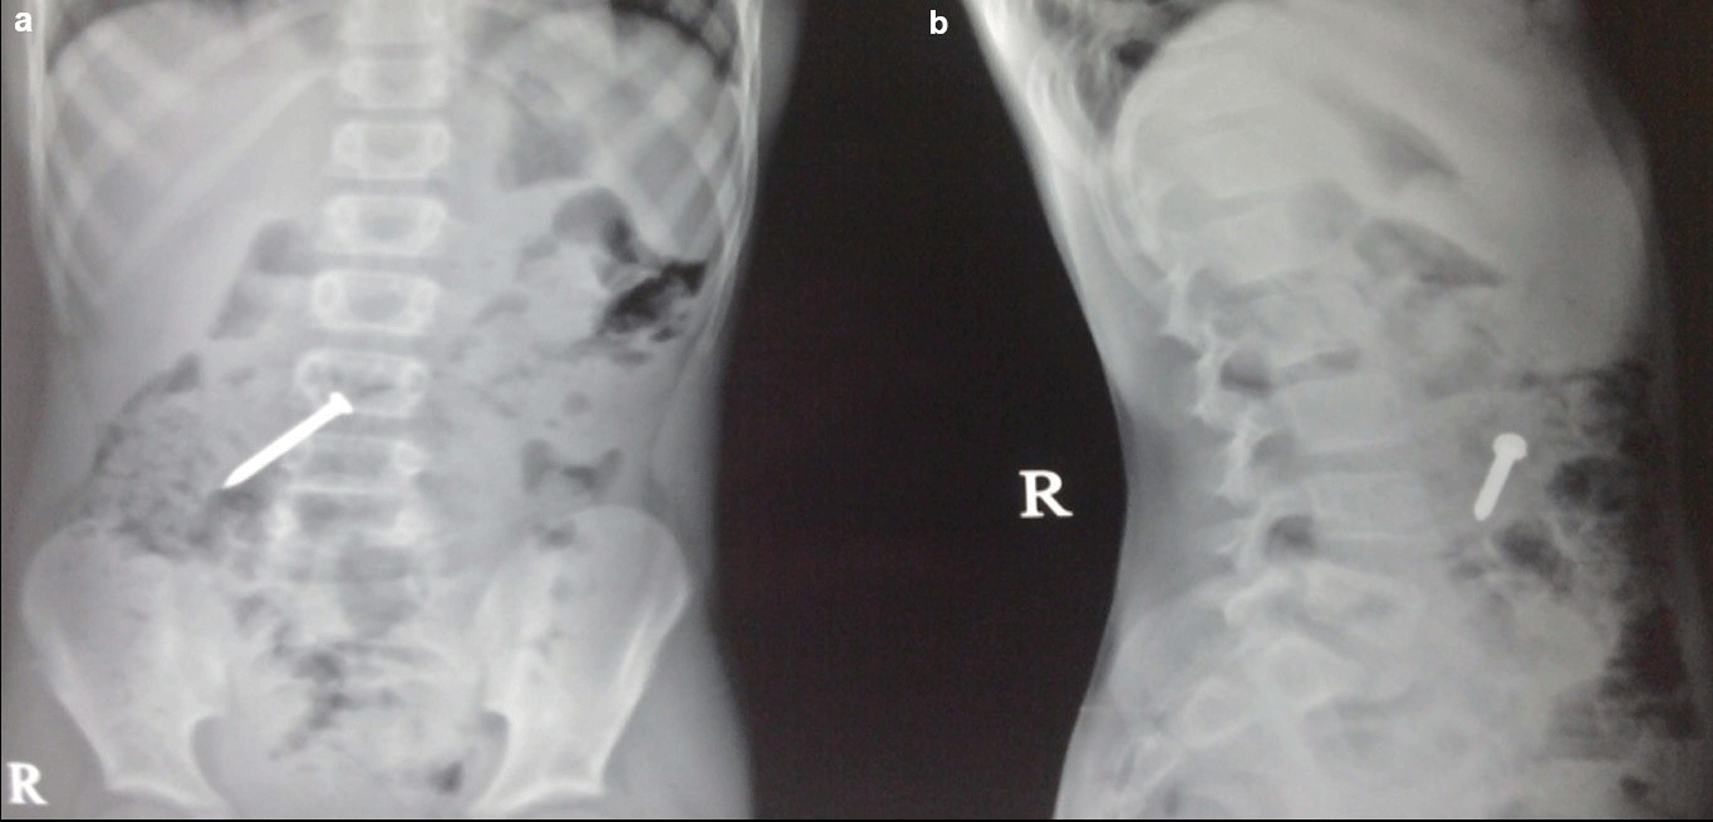

Case 3: A 25-year-old male patient came for ultrasound examination with complaints of pain in the abdomen for two-three months. Radiograph of the chest and abdomen reveal multiple linear radio-opacities in the left hypochondriac and lumbar quadrants of the abdomen, and a plain CT scan shows multiple hyperdense linear metallic foreign bodies within the gastric lumen, many piercing the gastric wall partially without any evidence of perforation. On laparoscopy, multiple refills of the pen and wires were found in the stomach, which were removed.

The swallowing of foreign bodies is a common condition in children and mentally challenged individuals.3–5 Fortunately, most ingested objects move through the digestive system without causing any problems (Figure 1a,b). Sharp and elongated objects can pass uneventfully (Figure 2a,b); however, they can pierce the mucosal lining and seriously damage or completely perforate the intestinal wall (Figure 3a-e). The object may just partially puncture the gut wall, resulting in a chronic inflammatory condition with few symptoms that is diagnosed months or years later.5–7

On laparoscopy, multiple refills of the pen and wires were found in the stomach, which were removed (e).